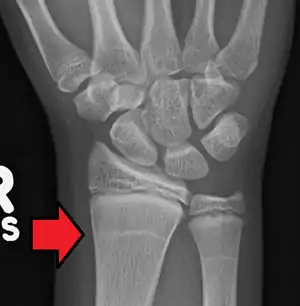

Growth arrest lines, also known as Harris lines, are lines of increased bone density that represent the position of the growth plate at the time of insult to the organism and formed on long bones due to growth arrest. They are only visible by radiograph or in cross-section. The age at which the lines were formed can be estimated from a radiograph. Harris lines are often discussed as a result of juvenile malnutrition, disease or trauma. Other studies suggest a reconsideration of Harris lines as more of a result of normal growth and growth spurts, rather than a pure outcome of nutritional or pathologic stress.[1] The lines are named after Henry Albert Harris, 1886-1968, professor of anatomy at the University of Cambridge.[2]

| Growth arrest lines in a child with an underlying bone disease | |